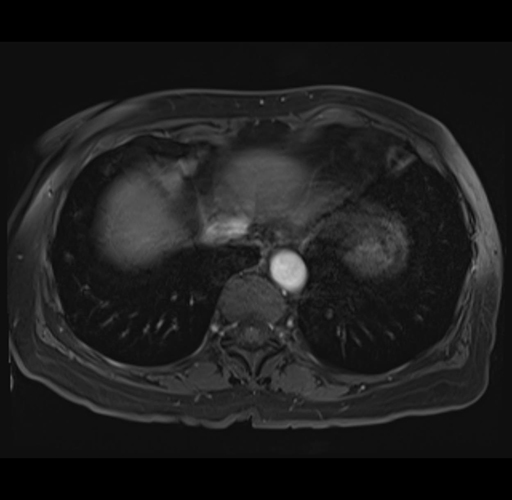

MRI T1